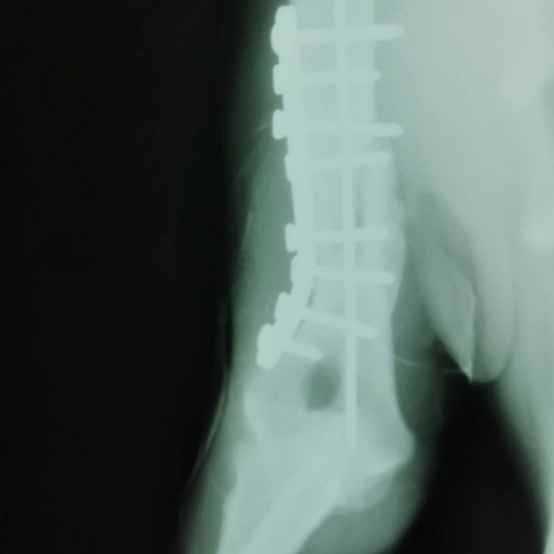

ไททัน

เพศ: เพศผู้

อายุ: 1 ปี, 7 เดือน 25 วัน

ลักษณะ: สายพันธุ์ไทย สีครีม

อาการ/โรค: ถูกรถชนขาหัก